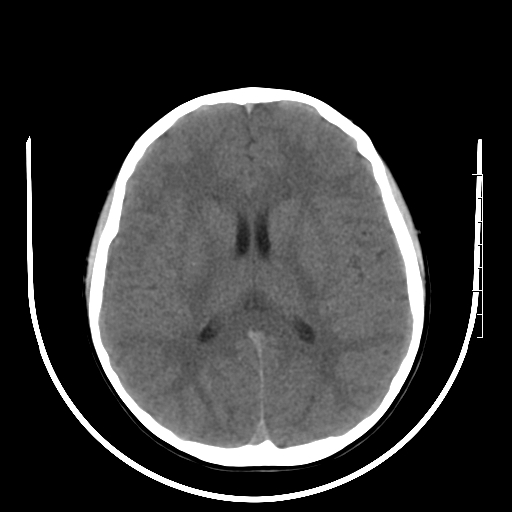

标题: PED3377:m、9y,恶心、呕吐,每月发作2-3次。 [打印本页]

标题: PED3377:m、9y,恶心、呕吐,每月发作2-3次。

右侧基底节区见钙化灶

右侧壳核多枚点状钙化灶。去请结合临床。

右侧壳核多枚点状钙化灶,请结合临床。

右侧壳核多发钙化灶,请结合临床。